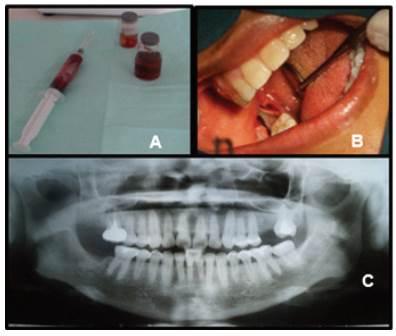

After preparing the treatment plan, the patient was asked to sign the informed consent form, and preoperative laboratory tests were ordered. As typical values were found, we decided to perform the aspiration test and subsequent excisional biopsy

Aspiration was performed before the excisional biopsy. Abundant bloody fluid and traces of tiny granules of apparent necrotic tissue were found (Fig. 3A). Total enucleation was performed. A single retromolar incision was made under local lower truncal anesthesia to open the vestibular and lingual flaps. The lesion was isolated entirely for subsequent enucleation (Fig. 3B), followed by thorough curettage and lavage of the bone cavity with abundant sterile saline solution. Tooth 4.7 was extracted and sutured with polypropylene to prevent recurrence. Painkillers, intramuscular anti-inflammatories and antibiotics, and alcohol-free mouthwash were prescribed.

The sample obtained was placed in 10% formalin and sent for histopathological study (Fig. 3A). The sections studied showed flat stratified epithelium with inflamed stroma and a corrugated parakeratinized surface, with basal cells with hyperchromatic nuclei. In some areas, the epithelium was separated from the cystic capsule, which confirmed the diagnosis of parakeratinized odontogenic keratocyst.

The sutures were removed, and the first postoperative control was performed ten days later. Three months later, the patient was seen for a clinical check-up and an evaluation with a panoramic radiograph. The radiograph showed excellent healing, no recurrence, and bone neoformation in the region of the lesion (Fig. 3C). Tooth 4.6 tested positive for pulp vitality.